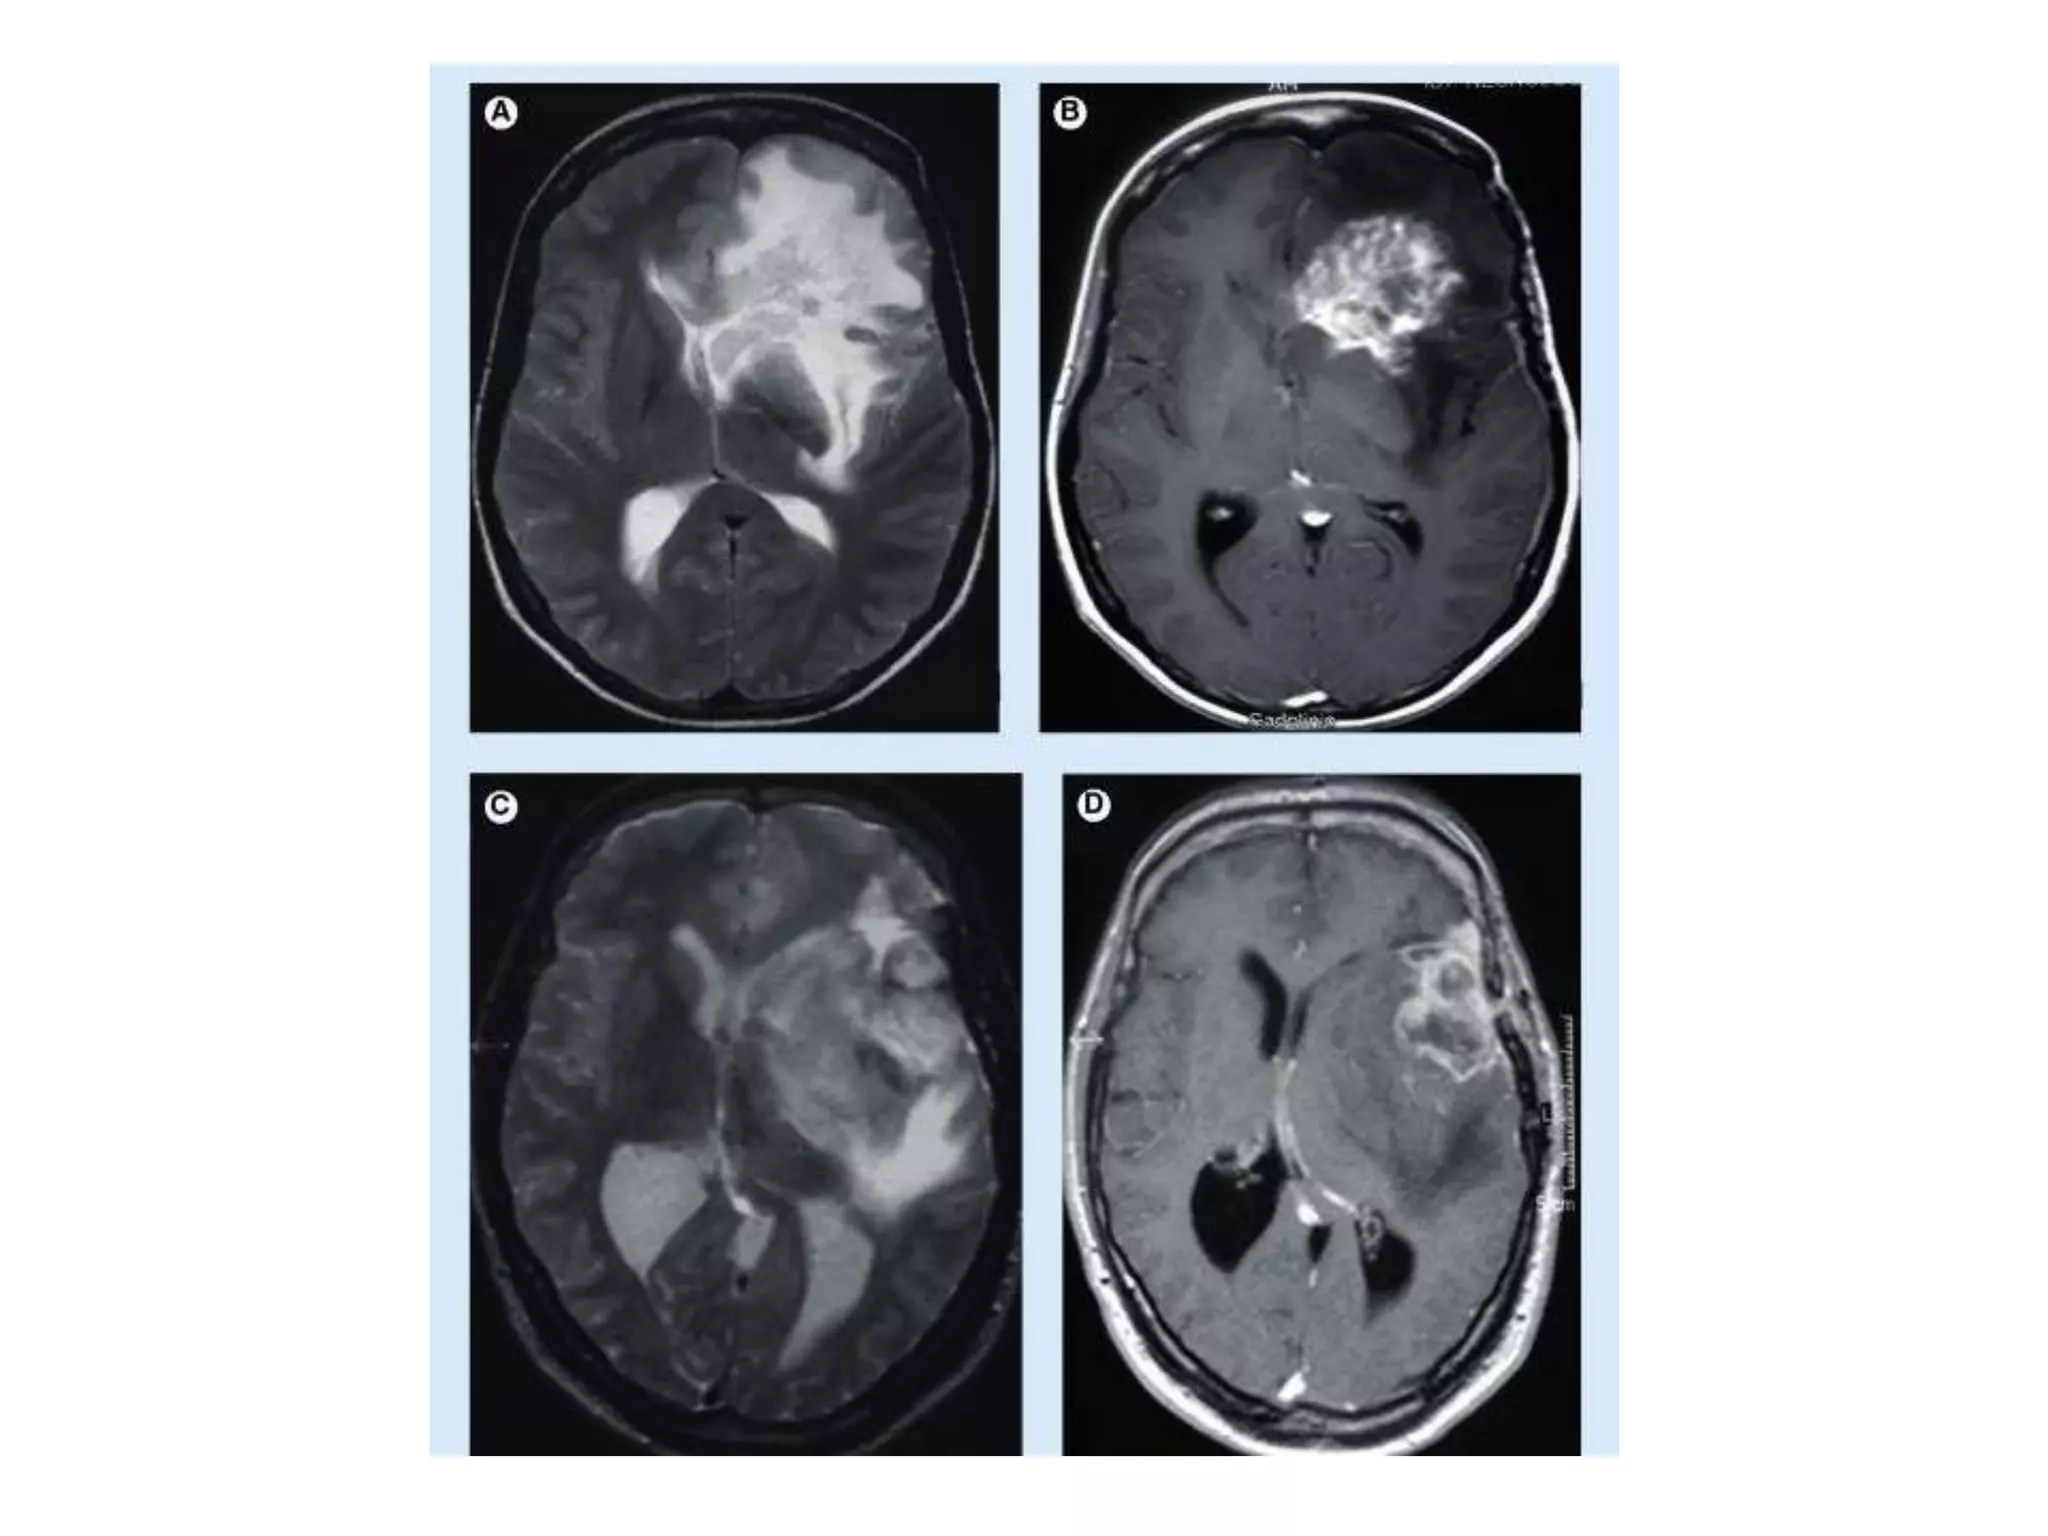

Vasogenic edema:

underlying mechanism for vasogenic edema.

The amount of edema is greatest in the white matter (increased water and sodium in the

extracellular spaces, decreased potassium); but the same changes may take place in grey

matter but less so.

The astrocytes become swollen.

• This type of edema is seen in response to trauma, tumors,

focal inflammation, and late stages of cerebral ischemia.

Interstitial oedema:-

• CSF pushed into extracellular space in

Cytotoxic edema:

• This is due to the derangement in cellular metabolism

resulting in inadequate functioning of the sodium and

potassium pump in the glial cell membrane.

As a result there is cellular retention of sodium and water.

There are swollen astrocytes in grey and white matter.

• Cytoxotic edema is seen with various intoxications

(dinitrophenol, triethyltin, hexachlorophene, isoniazid) and

in Reye's syndrome, severe hypothermia, and early

ischemia.